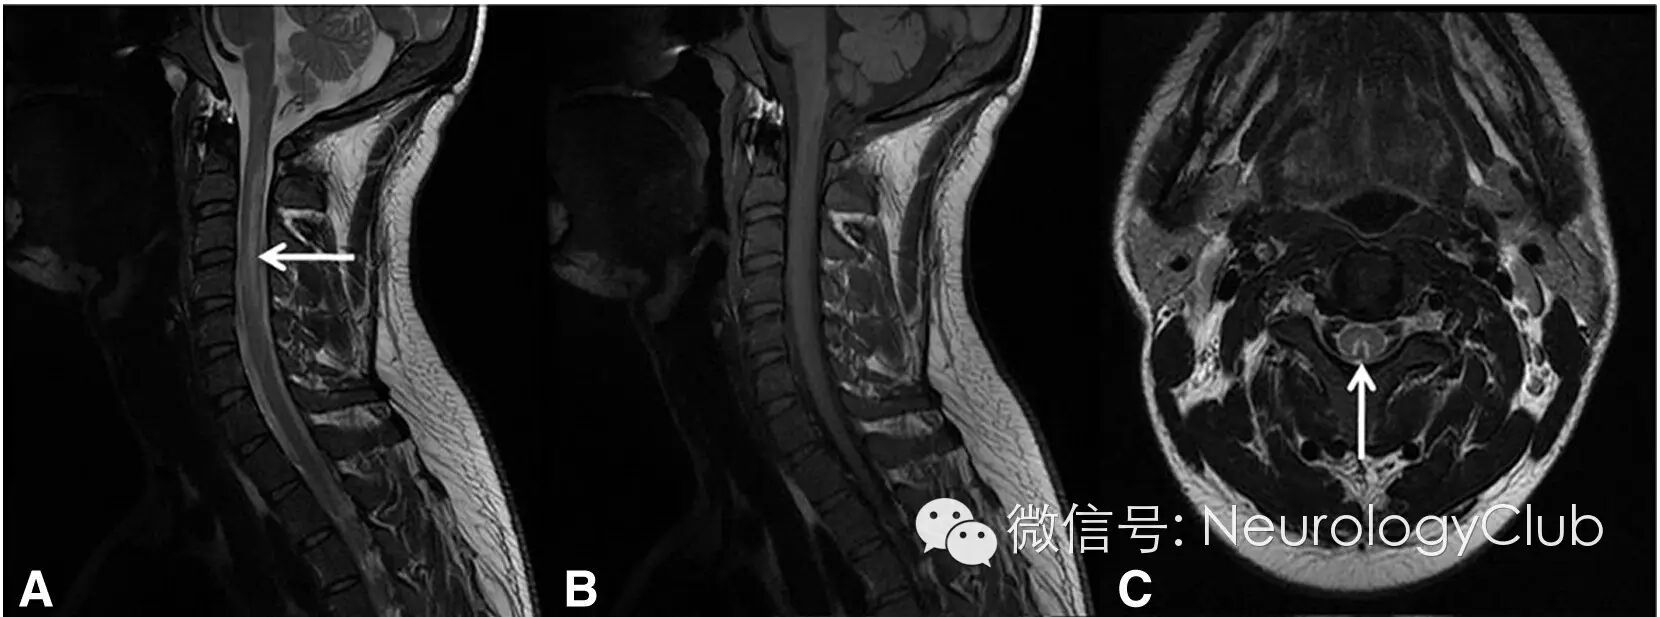

1视神经脊髓炎

(AQP4阳性的NMO患者。A-B:C2-T10可见长节段脊髓病灶,脊髓中央水肿,呈T2WI高信号,T1WI低信号;C:横断面T2WI脊髓周围白质未受累)